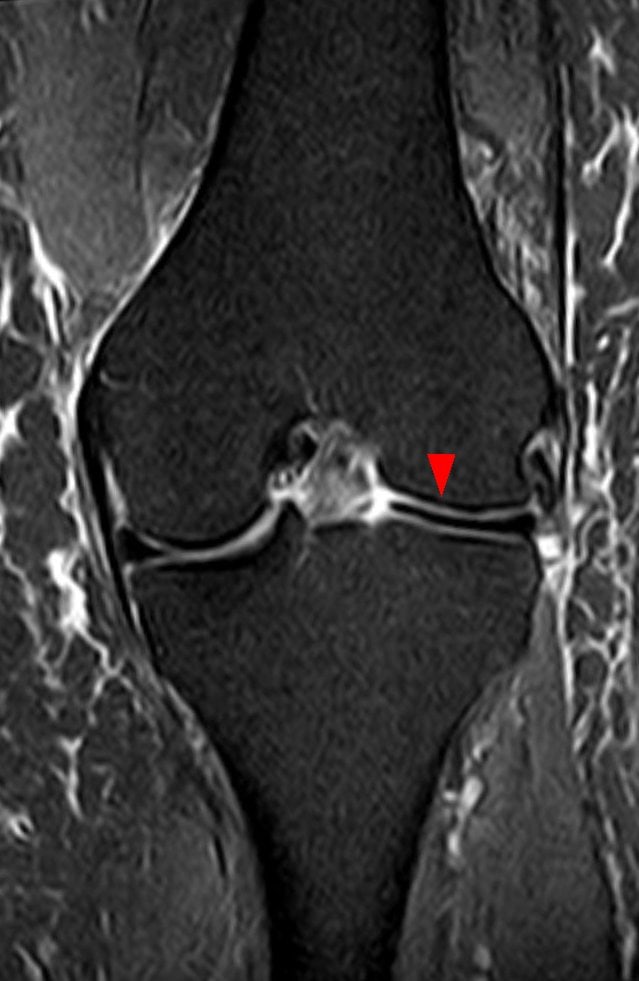

Meniscus Syndrome and Knee Disorders

In soccer players, meniscal injuries manifest as a complicated syndrome including swelling, discomfort, and mechanical signs inside the knee. Dealing with forces of 5–8 times body weight during running exercises, the menisci serve as shock absorbers and load distributors.

Repetitive loading cycles, particularly on tougher playing surfaces or with insufficient shoes, cause chronic meniscal disorders to manifest slowly. Usually caused by rotational movements combined with knee flexion, acute meniscal tears frequently impact the medial meniscus because of its strong capsular connections.

Conservative treatment includes activity modification, anti-inflammatory procedures, and strengthening regimens aimed at the quadriceps and hamstring muscle groups. Mechanical symptoms or ongoing pain restricting performance may call for surgical intervention using arthroscopy. Still, one must seriously assess the long-run effects of meniscal surgery, including a higher chance of osteoarthritis.